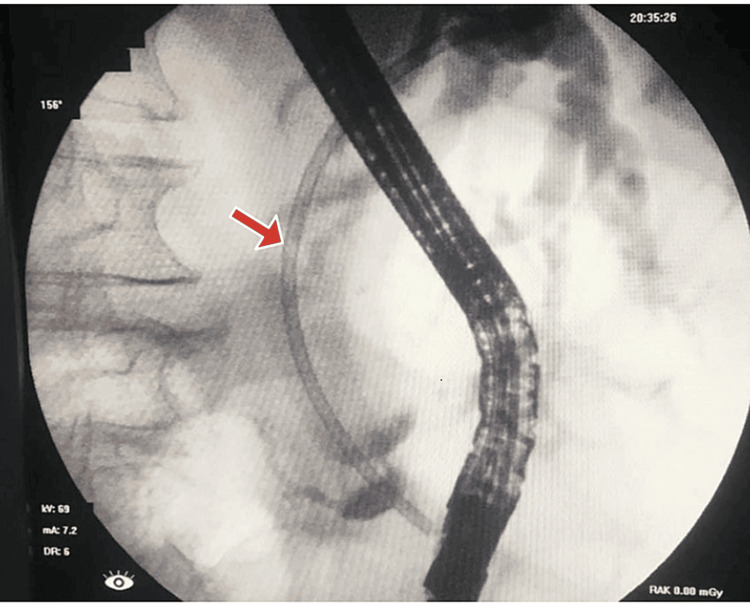

The planned ERCP showed a limited view and revealed a normal esophagus, stomach, and duodenum. The ampulla appeared bulging and downlooking, making cannulation difficult and requiring more than 5 minutes. Initially, the pancreatic duct (PD) was cannulated, and dye was injected. Consequently, a 7Fr x 7cm plastic stent was placed into the PD following a limited sphincterotomy. After post-PD stenting, CBD was selectively cannulated into the right hepatic system, and dye injection showed grossly dilated CBD and IHBCs with a narrow segment at the distal end of the CBD. A 10Fr x 10cm plastic biliary stent was placed across the narrow segment, allowing free flow of bile and dye. ERCP showed a distal CBD stricture, suggestive of malignancy. The patient’s CA 19-9 level was significantly elevated (>12,000), further supporting the suspicion of a malignant process. Figure 2 shows the cholangiogram, which revealed a grossly dilated CBD and IHBC dilatation with a narrow segment at the distal end of the CBD. A plastic stent, facilitating bile flow, can be seen in place.